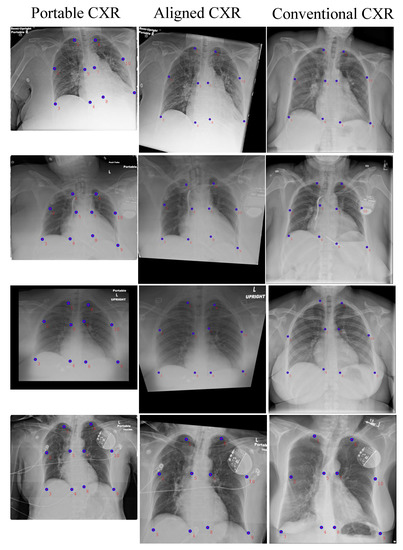

- Firstly, we introduce a novel database collection of subject-pairs radiographs. For each subject, we collect a pair of samples which are from both portable machines (source domain) and conventional machines (target domain).

- Secondly, we introduce a new deep learning-based approach to align a subject-pairs dataset to obtain pixel-pairs dataset. In order to learn the knowledge correlation between two different domains, it is important to have a pixel-wise pair dataset. Thus, alignment is an important step that helps to perform knowledge transferring from the source domain to target domain.

4.3.1. CXR Alignment Network